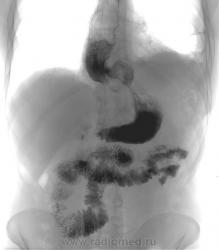

Случай третий...из той же оперы...проблема (какая?) решена...(как?)....

Последние три снимка - до операции за 2006 и 2007 годы...

В предпоследнем случае, если я правильно рассмотрел, анастомоз в средней трети желудка по задней стенке?

В последнем случае пластика кардии, только не пойму чем.

Все правильно  по второму случаю; правильно и третьему, только там просто пластика, без замены фрагмента, а причина известная, рубцовое сужение...

Снимки до последней операции - за 2006 и 2007 гг., сделаны с временной экспозицией не менее 40 мин отначала исследования.